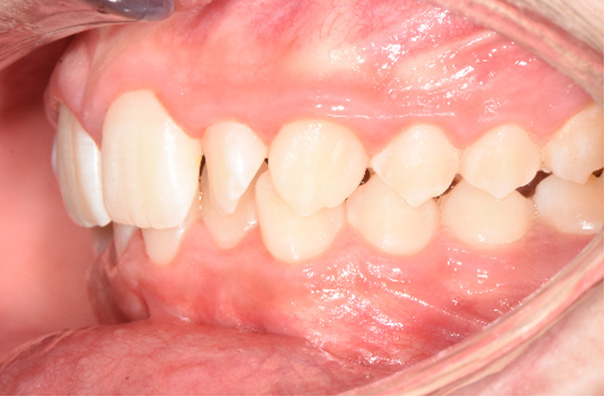

A 14-year-old male patient presented with a Class II sub-division 2 malocclusion with significant maxillary and mandibular crowding. The facial profile was convex with a slightly retrusive mandible, tendency to deep bite. Normal upper and lower first incisor inclination was measured, protruded upper and lower lip were noted. A constricted arch form with tapered buccal segments resulted in poor smile width and dark buccal corridors. Along with a reverse smile arc due to insufficient incisor eruption, this resulted in poor smile aesthetics.

The objectives were to create space while maintaining maxillary incisor position, improve the smile arc by erupting incisors, and develop the posterior segments for increased arch length, as well as improved smile width. Resolving crowding through arch development with proper torque control was a key objective, since incisor advancement and increased angulation would damage smile aesthetic and would result in a more pronounced lip. A non-extraction plan was chosen using Damon Ultima PSL System with Ultima wires, along with the use of anterior bite turbos and light elastics for early deep bite and Class II correction.

Observations: Arch form was really improved in both shape and width. The variable torques allowed the Ultima wires to express the deflection and the torque changes were very close to the final goals. The time frame was 3 months.